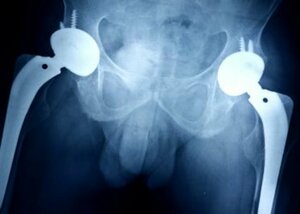

Hip Replacement